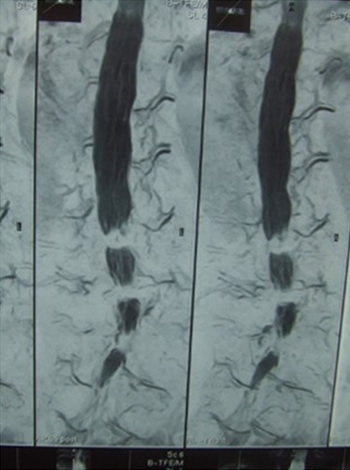

The mechanism of intermittent claudication is as follows. In scoliosis, the cauda equina nerve, which is located below the second lumbar vertebra. It resembles a horse's tail and is compressed by a deformed yellow ligament or vertebra causing pain and numbness in the lower extremities. The cauda equina nerve has longitudinally distributed blood vessels that supply oxygen and nutrients to the nerve root as shown in Figure 2-2.

As the lumen of the lumbar spinal canal narrows, the nutrient vessels of the caudal nerve are compressed and narrowed. When the lumbar spine kyphosis is strengthened by upper body loading (60% of body weight) during walking, the spinal canal is further narrowed and the pressure on the blood vessels becomes stronger. As a result, blood flow to the cauda equina nerve deteriorates, causing pain and numbness in the lower limbs, making walking difficult (intermittent claudication).

Thus, the mechanism of the pain, numbness, and burning sensation in the hip and lower limbs during walking is due to the blood flow disturbance caused by the compression of the blood vessels that nourish the spinal cord. New meridian therapy effectively improves numbness and pain during walking without the need for surgery. The mechanism of this effect is thought to be that it improves blood flow around the spinal canal and spinal blood vessels, reduction of edema due to inflammation of the tissues around the spinal canal, thereby improving the narrowing of the spinal canal. At the same time it repairs and expands the spinal blood vessels, thereby improving blood flow.

Figure 2-8. Stenosis of L3/4, L4/5, and L5/S1 - Treatment course